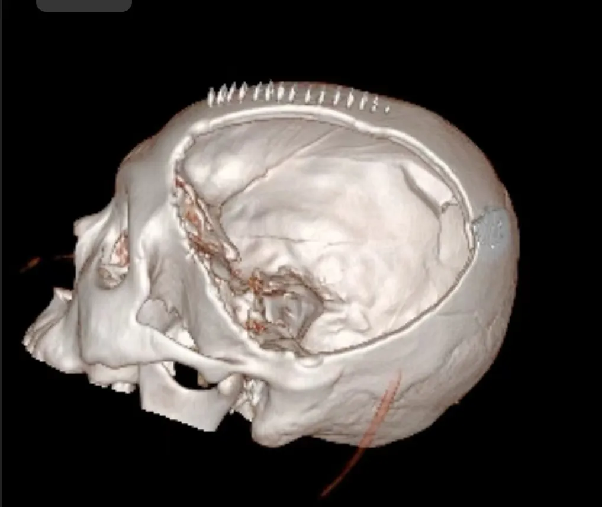

患者汪某,男性,66歲,因重症顱腦(nǎo)損傷,多發肋骨(gǔ)骨折,血氣胸,鎖骨骨折辦理入院緊急手術,醫院神經外科專家團隊為患者行開顱血腫清除+大骨瓣減壓術。手術順利,術後(hòu)恢複滿意。專家團隊將患者手術去除的顱骨骨瓣進行了清洗、滅菌後低(dī)溫冰凍儲存。

患者術後滿三個月(yuè)再次返院進(jìn)行顱骨缺損(sǔn)修補術,經過完善術前檢查、全(quán)科討論、做好充分手術(shù)準備後,武(wǔ)寧縣總醫院人民醫院院區神(shén)經外科團隊成功為患者完成(chéng)自體顱骨修補術(shù)。

術後: